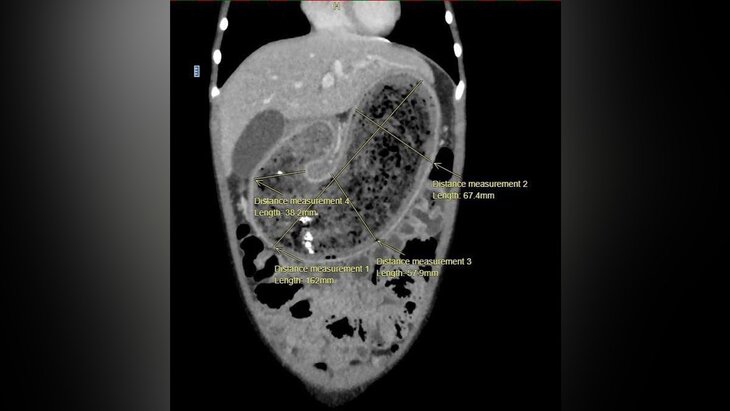

Во время первичного осмотра медики обнаружили заметное образование, выпирающее на передней стенке желудка. Проведенная компьютерная томография подтвердила наличие огромного трихобезоара, который полностью заполнил желудок, двенадцатиперстную кишку и начальный отдел тонкой кишки.